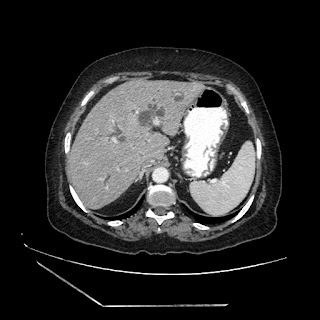

A 70 years old woman with Obstractive jaundice & palpable GB